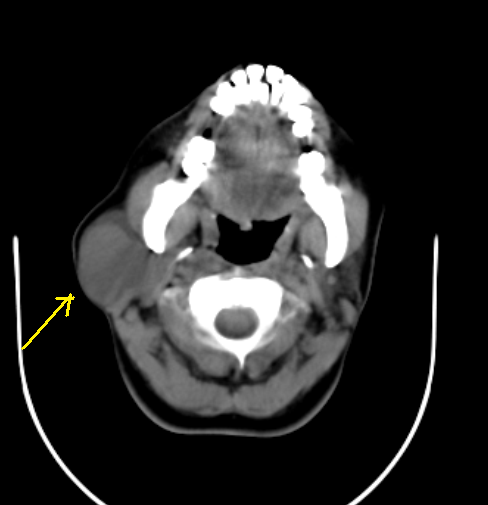

BRANCHIAL CLEFT CYST